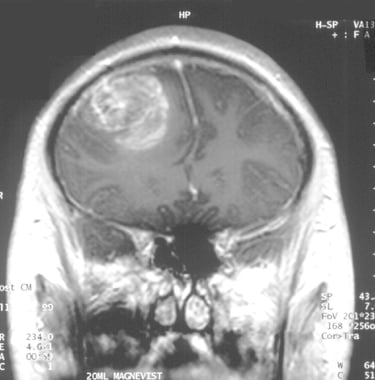

Çalışmanın Odak Noktası: Calgary Üniversitesi araştırmacıları, en agresif beyin kanseri türü olan glioblastomaya karşı, standart tedaviye (ameliyat, radyasyon, kemoterapi) ek olarak yüksek doz B3 vitamini (niasin) kullanımını araştırmaktadır.

Erken Dönem Sonuçları: 24 hasta ile yürütülen klinik denemelerin ilk aşaması oldukça olumludur. Hastaların %82'sinde 6 ay sonrasında hastalığın ilerlemediği görülmüştür. Bu oran, önceki standart tedavi verilerine kıyasla %28'lik dikkate değer bir iyileşme anlamına gelmektedir.

Uzman Uyarısı ve Süreç: Dr. Gloria Roldan Urgoiti ve Dr. Wee Yong gibi uzmanlar, yüksek doz vitamin tedavisinin ciddi yan etkileri olabileceğinden kesinlikle sıkı bir tıbbi gözetim altında yapılması gerektiği konusunda uyarmaktadır. Çalışmanın nihai ve kesin analizinin 2026 sonu veya 2027 başlarında tamamlanması planlanmaktadır.